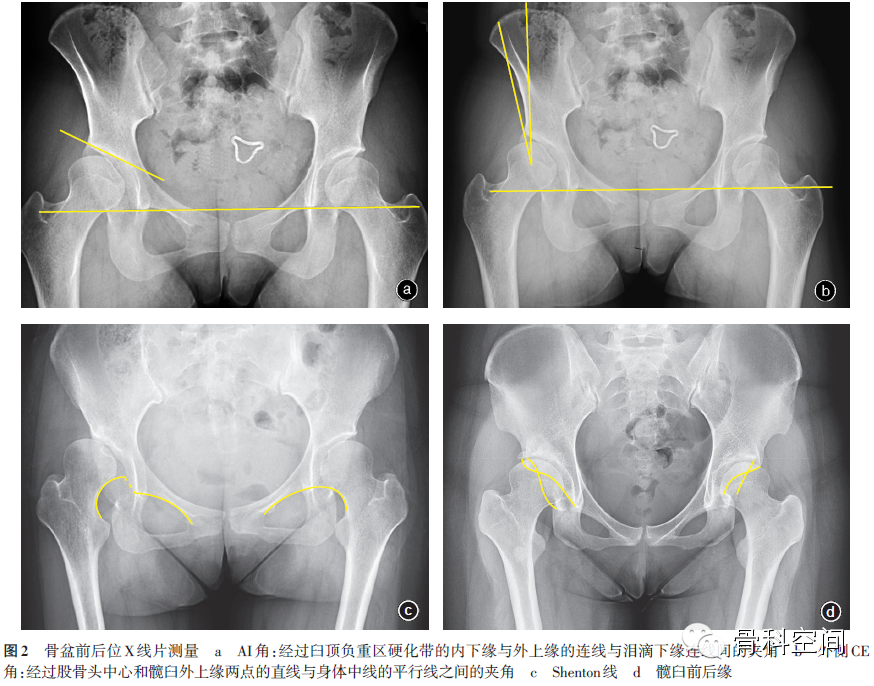

(一)骨盆前后位X线片:测量外侧CE角、臼顶倾斜(acetabular inclination,AI)角[10]、Shenton线,观察髋臼前后缘的位置[11-12]及股骨头形态等(图2)。